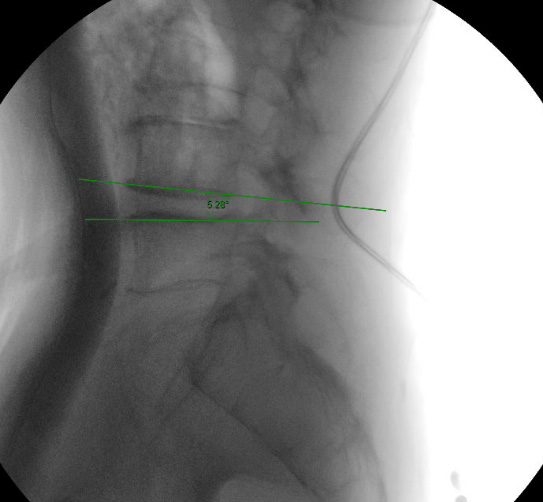

Preoperative (left) and postoperative (right) with interspinous device